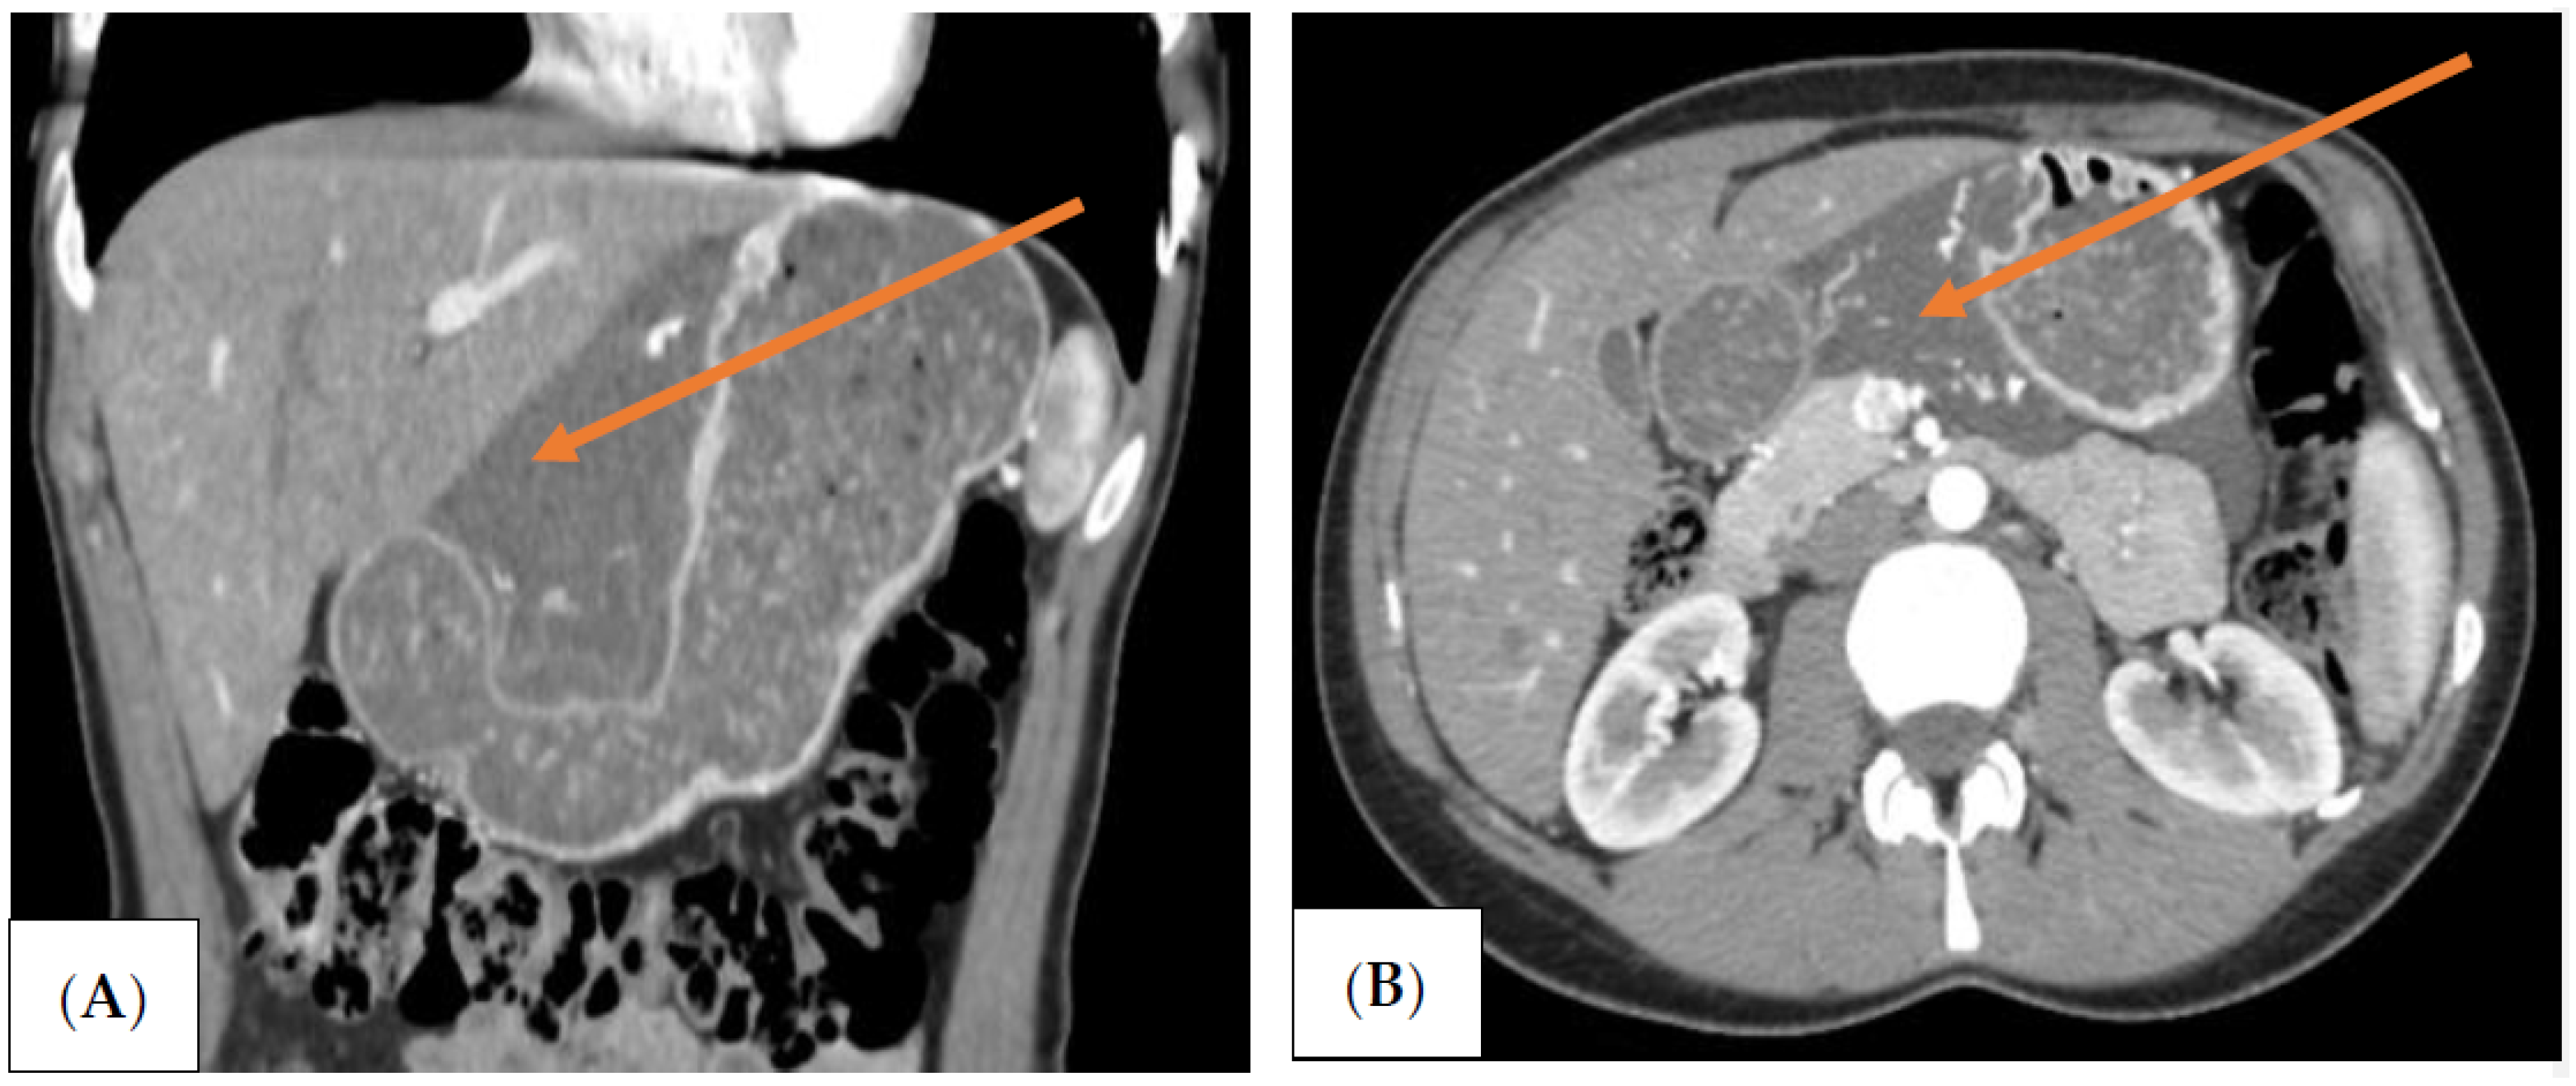

The patient was qualified for elective surgery. The presence of an approximately seven-cm long soft tissue extending along the lesser curvature of the stomach, closely connected to the stomach wall, was found intraoperatively (Figure 2). The tumour penetrated the gastrohepatic ligament, but did not reach the liver. The lesion did not penetrate the retroperitoneal space or infiltrate the pancreas. The tumour was completely removed without gastric wall resection (Figure 3). After removal of the lesion, the serosa of the lesser curvature of the stomach was secured with a continuous PDS 4/0 suture (Figure 4).

Figure 4. Intraoperative view after tumou r resection of the lesser curvature of the stomach. The arrows indicate the lesser curvature of the stomach (black arrow), and the front surface of the pancreas (orange arrow).